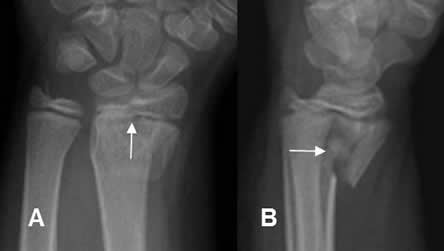

Fig 74 A. Salter tipo III.

A y B: Rx AP. Fracturas verticales en las epífisis del radio y el dedo, por lesiones tipo III.